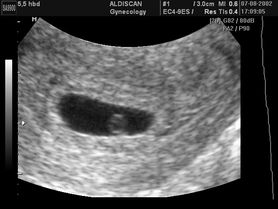

Płód w 5 tygodniu ciąży